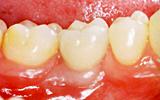

インプラントだと解りますか? | |||||||||||

| インプラント治療技術の進歩によって、自分の歯と殆ど見分けがつかないように治療することが可能になりました。しかし、インプラントは決して自分の歯にまさる物ではありません。まず、ご自分の歯を大切にして下さい。 | ![]() |

【術前】 |

【術後】 |